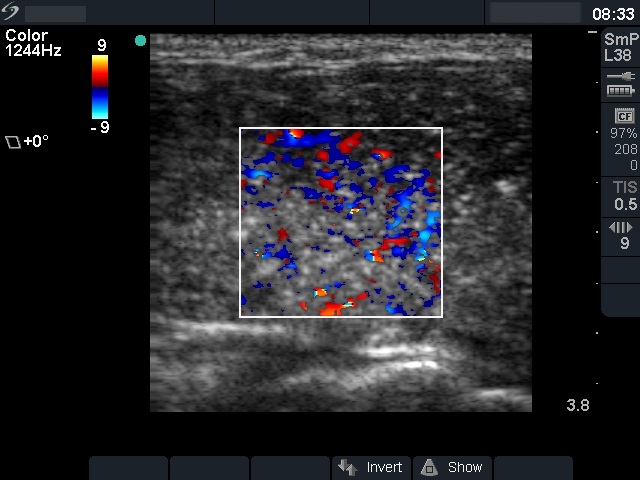

Follow-up examination 4 weeks after surgery (fourth and fifth rows):

Radioiodine treatment was planned. The patient visited us to get information about the prognosis of her disease.

Palpation: no abnormality.

Ultrasonography: There was no parenchyma in the thyroid beds. There were multiple enlarged lymph nodes in the lateral side of the neck. One of them very close to the thyroid seemed to be benign, reactive, but there was a chain of atypical, suspicious lymph nodes next to the strernocleidomastoid muscle.

Cytology: papillary cancer.

The patient was reoperated. Histopathology disclosed metastatic foci in the lymph nodes. 6 weeks later she underwent radio-iodine treatment.

3. The performance of ultrasound may have role after surgery (thyroidectomy and appropriate lymphadenectomy) but before radioiodine treatment. Ultrasound examination can reveal insufficiency of surgery in around 10 to 20% of such cases. Most of these cases occur when either the surgeon performed the exploration is relatively inexperienced or in cases where the diagnosis has not been made preoperatively and therefore the appropriate lymphadenectomy was not performed.